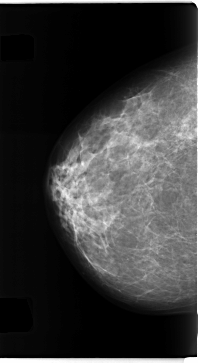

C_0271_1.RIGHT_CC

RIGHT_CC LINES 4712 PIXELS_PER_LINE 2568 BITS_PER_PIXEL 12 RESOLUTION 50 NON_OVERLAY